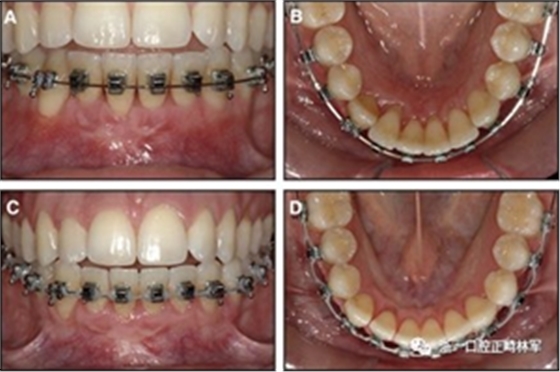

隨著時(shí)間的推移,全維度弓絲及其表達(dá)的牙齒間扭矩差異顯著改善(圖17)。明智的鄰間減少之后,間隙關(guān)閉擴(kuò)大接觸面,消除不美觀的黑三角。在脫粘之前也校正了牙齒排列和牙弓形態(tài)(圖18)。

之前和之后的三維圖像(圖19)突出顯示在下頜右側(cè)尖牙面?zhèn)缺砻嫔瞎堑脑黾右约扒把姥栏恢玫母纳啤S捎谙骂M切牙的伸長(zhǎng)被認(rèn)為是不嚴(yán)謹(jǐn)?shù)?,因此輕度前牙開(kāi)合沒(méi)有被矯正。

圖17.治療進(jìn)展:A和B,二次手術(shù)后愈合; C和D,幾個(gè)月后牙根扭矩的改善。

圖18.脫粘后的最終圖像:A,正面視圖; B,咬合面視圖。 進(jìn)一步的牙齒移動(dòng)以糾正輕度前牙開(kāi)合被認(rèn)為不符合患者的最佳利益。